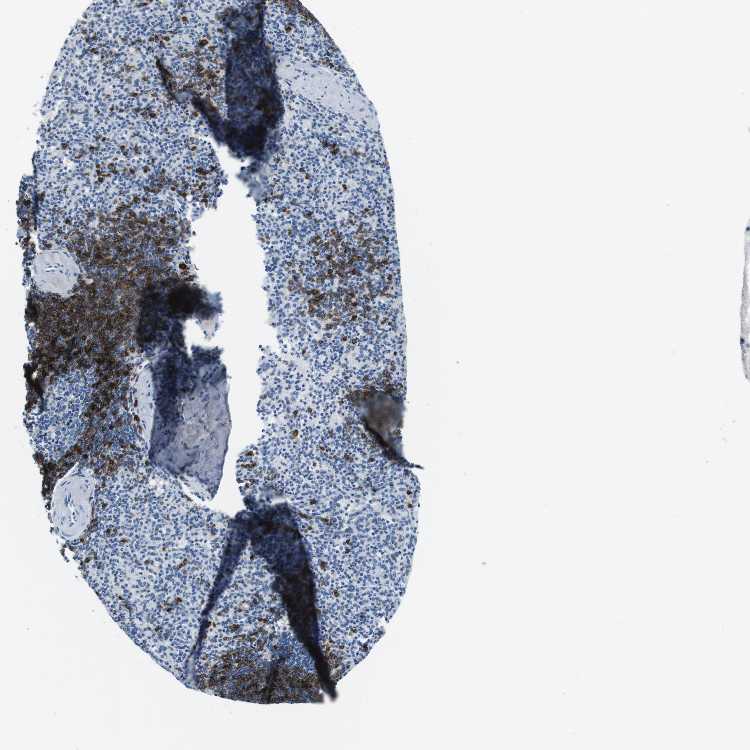

SPLEEN - Antibody stainingi

Antibody staining in the annotated cell types in the current human tissue is reported as not detected, low, medium, or high, based on conventional immunohistochemistry profiling in selected tissues. This score is based on the combination of the staining intensity and fraction of stained cells.

Each image is clickable and will lead to virtual microscopy that enables deeper exploration of all samples and also displays staining intensity scores, fraction scores and subcellular localization as well as patient and tissue information for each sample.

Antibody CAB012703

Cells in red pulp Not detected

Cells in white pulp High